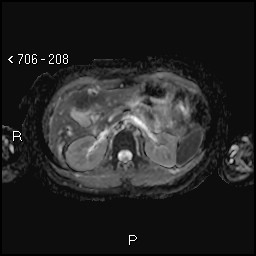

Aspetti RM: minuto nodulo della testa pancreatica ipointenso in T1.

image